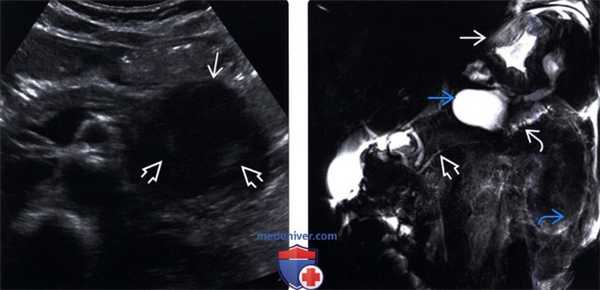

(Левый) Трансабдоминальное УЗИ, поперечное сканирование: гетерогенное образование в области хвоста поджелудочной железы, состоящее из множественных мелких кист, разделенных перегородками, эхогенность которых повышена, вследствие большого количества отражающих поверхностей.

(Правый)Аксиальная КТ с контрастированием: классическая ячеистость серозной цистаденомы: микрокистозное поражение с тонкими эхогенными перегородками, очерчивающими мелкие кисты. Обратите внимание на диффузную центральную кальцификацию и отсутствие утолщения стенок, что также является характерными признаком. (Левый) Трансабдоминальное УЗИ, поперечное сканирование: анэхогенное кистозное поражение, с четким контуром, в области тела поджелудочной железы, с несколькими гиперэхогенными периферическими очагами.

(Правый) Аксиальная КТ с контрастированием: гиподенсное образование овальной формы без капсулы в области тела поджелудочной железы, с утолщенной контрастной стенкой. Образование содержит внутренние перегородки, не визуализирующиеся на КТ. (Левый) Трансабдоминальное УЗИ в режиме цветовой допплерографии, поперечное сканирование: скопление множественных мелких кист, округлой и овальной формы в области тела поджелудочной железы.

(Правый) Аксиальная МРТ в режиме Т2 HASTE у этого же пациента лучше визуализирует мультиочаговое поражение поджелудочной железы. Множественные кисты высокой интенсивности в режиме Т2 визуализируются вдоль поджелудочной железы, несколько из них прилежат к расширенному протоку, что соответствует смешанной внутрипротоковой папиллярно-муцинозная опухоли, поражающей как главный панкреатический проток, так и его ответвления. (Левый) Трансабдоминальное УЗИ, поперечное сканирование поджелудочной железы: визуализируется округлое кистозное поражение с четким контуром, имеющее экзофитный тип роста, исходящее из области шейки поджелудочной железы. Была выполнена биопсия под контролем эндоскопического УЗИ, которая подтвердила диагноз: кистозная нейроэндокринная опухоль поджелудочной железы.